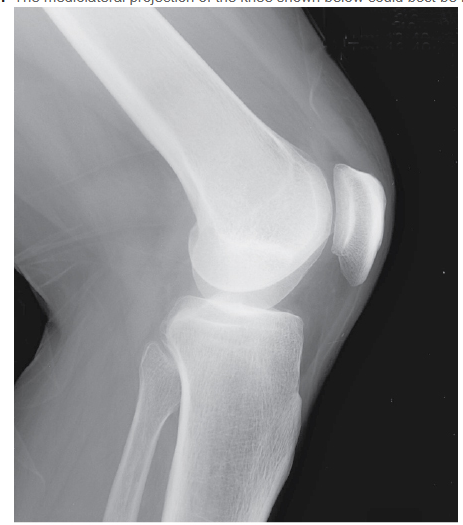

To improve this view of the mediolateral knee, how could it be improved?

A - rotating the patient forward

B - rotating the patient backward

C - angling the central ray (CR) about 5 degrees caudad

D - angling the CR about 5 degrees cephalad

A

The knee is formed by the proximal tibia, the patella, and the distal femur, which articulate to form the femorotibial and femoropatellar joints. The distal posterior femur presents two large medial and lateral condyles separated by the deep intercondyloid fossa. Because the medial femoral condyle is further from the IR, it is magnified and will obscure the femorotibial joint space, as seen in the figure. If the CR is angled about 5 degrees cephalad, the medial femoral condyle will be projected superiorly and superimposed on the lateral femoral condyle, thus opening the joint space. The patient should lie on the affected side with the patella perpendicular to the tabletop and the knee flexed 20 to 30 degrees. Rotating the part forward or backward will affect visualization of the femoropatellar joint.